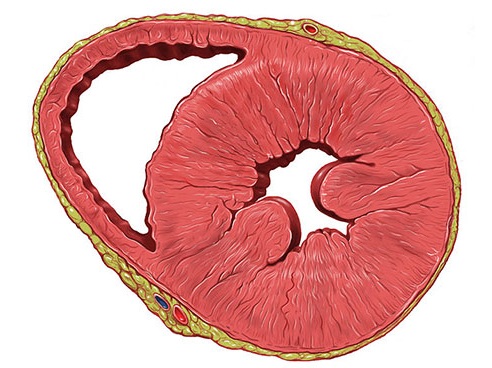

ARVC以右心室的脂肪浸润为主要特征(如下图所示),从而导致RV肥大,可能导致致命的心律失常。在兰尼碱钙通道受体异常也有报道。

ARVC多见于意大利北部威尼托地区居民(及其后代),被认为是常染色体显性遗传。这种疾病的初期表现为心源性猝死;因此,筛查患者的家庭成员是确诊新病例的关键。